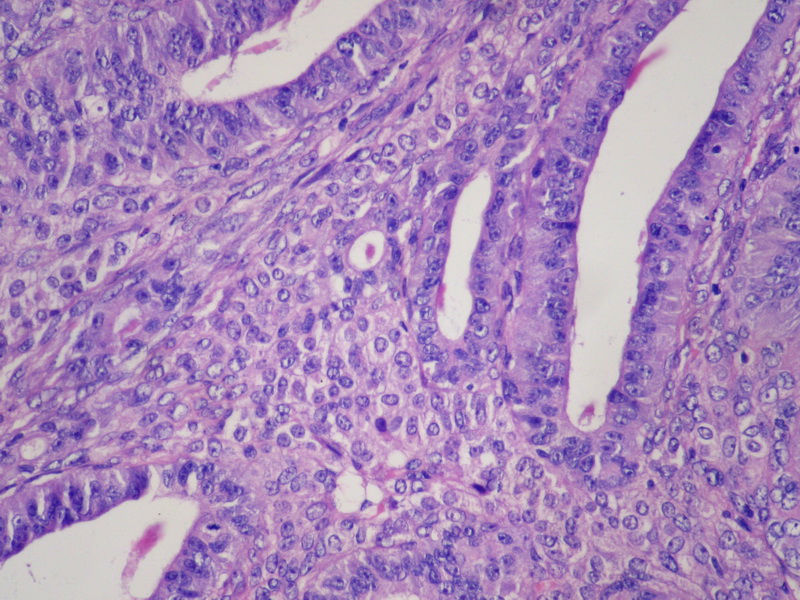

76岁女性,绝经20余年,阴道流血10天。超声示左卵巢肿物。

左卵巢肿物大小7*6*6CM,切面囊实性,含血性液体,实性区域灰白色。

请教的问题是:inhibin-a阳性的细胞是什么?这例应诊断什么肿瘤?

76岁女性,绝经20余年,阴道流血10天。超声示左卵巢肿物。图1

卵巢子宫内膜样腺癌

本例有典型的高分化子宫内膜样腺癌的区域。

高分化子宫内膜样腺癌,中间那点可能是高雌激素下卵巢间质反应,也可能是伴性索间质的成分。如果片中只有那些我认为可以忽略不计,如果很多要深究一下。